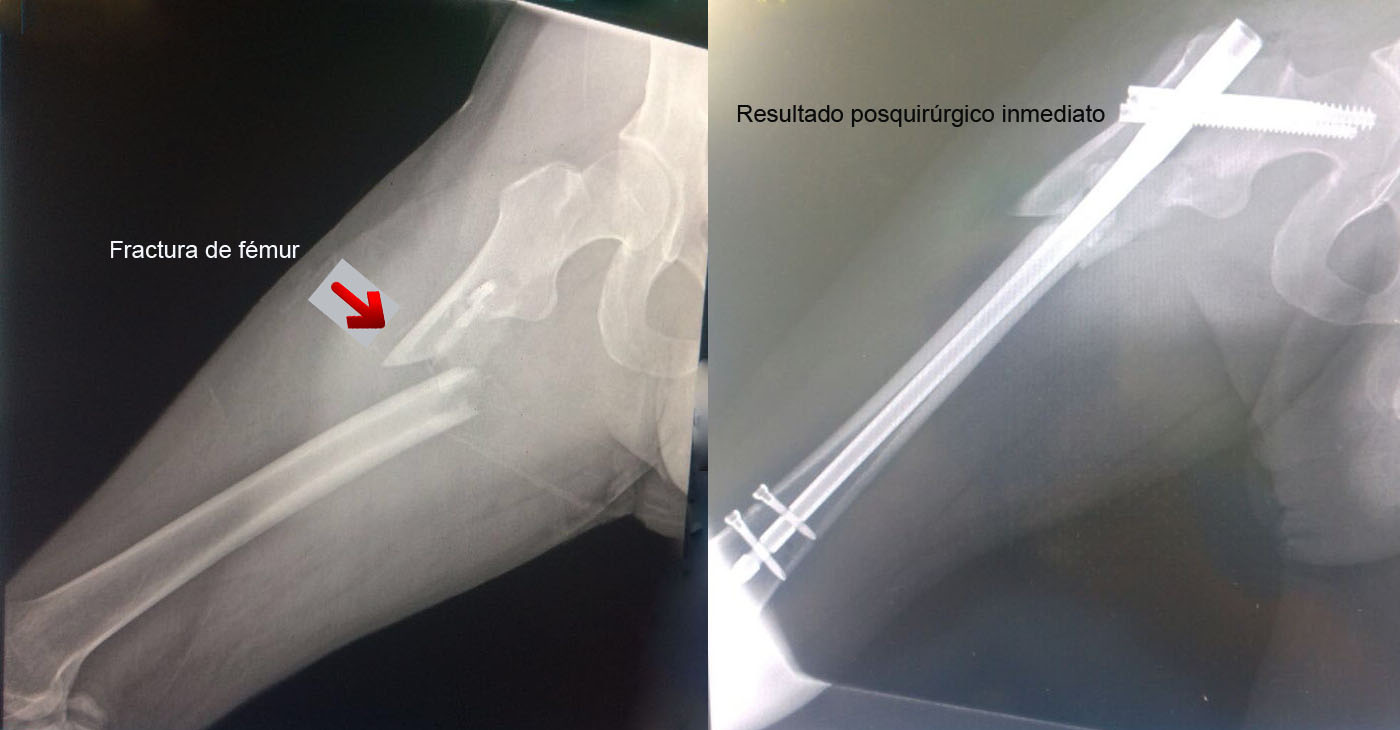

Una fractura ósea es la ruptura de un hueso, la cual puede presentarse por diversas causas y su tratamiento dependerá de la magnitud, sitio anatómico y de las enfermedades concomitantes. Algunas pueden manejarse de forma conservadora con solo inmovilización y hay otras que requieren de un tratamiento quirúrgico. A continuación, podrá ver algunos casos quirúrgicos, dando clic a la zona del cuerpo afectada.